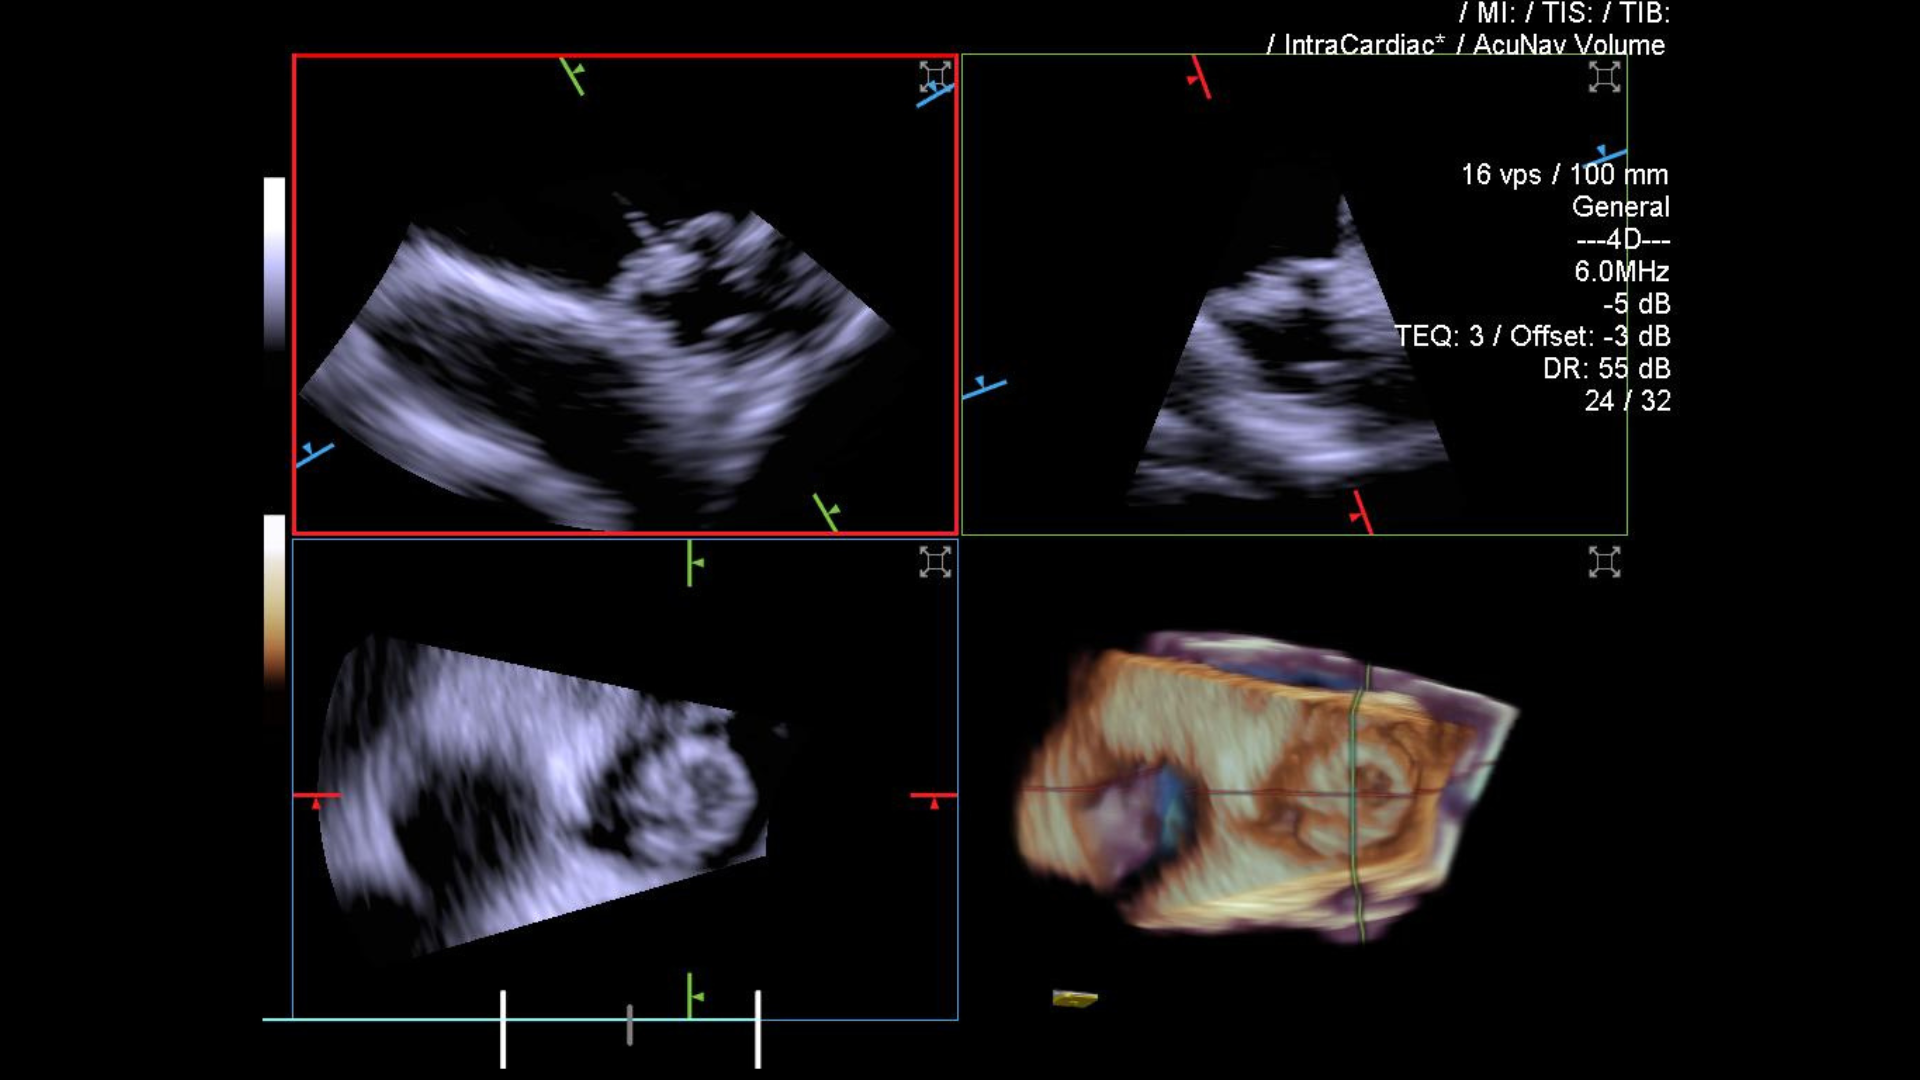

Ice Catheter Siemens .  introducing the acunav lumos 4d ice catheter, delivering incredible image quality and precise procedural guidance. In matters of the heart, visualization matters. Learn more about our newest.   the acunav volume ice catheter transforms care delivery by enabling treatment of patients who were.  with the acuson acunav volume 4d ice catheter, you can take on the most complex cases with the highest standard in.   acuson acunav volume ice catheter.   siemens healthineers has received ce mark for the acunav volume ice (intracardiac echocardiography) catheter, which is a. See full details of the heart in dynamic 4d motion even while imaging patients in.  * the acuson acunav 4d ice catheter enables precise orthogonal plane measurements with reference planes.  acuson acunav volume ice catheter. This is command, in your hands.   according to siemens, the acunav volume ice catheter enables treatment of patients who were previously.

with the acuson acunav volume 4d ice catheter, you can take on the most complex cases with the highest standard in.   siemens healthineers has received ce mark for the acunav volume ice (intracardiac echocardiography) catheter, which is a. See full details of the heart in dynamic 4d motion even while imaging patients in.  introducing the acunav lumos 4d ice catheter, delivering incredible image quality and precise procedural guidance.  acuson acunav volume ice catheter.  * the acuson acunav 4d ice catheter enables precise orthogonal plane measurements with reference planes.   according to siemens, the acunav volume ice catheter enables treatment of patients who were previously.   the acunav volume ice catheter transforms care delivery by enabling treatment of patients who were. Learn more about our newest.   acuson acunav volume ice catheter.

Ice Catheter Siemens  In matters of the heart, visualization matters. In matters of the heart, visualization matters.   acuson acunav volume ice catheter. Learn more about our newest.  introducing the acunav lumos 4d ice catheter, delivering incredible image quality and precise procedural guidance.  with the acuson acunav volume 4d ice catheter, you can take on the most complex cases with the highest standard in.   siemens healthineers has received ce mark for the acunav volume ice (intracardiac echocardiography) catheter, which is a.  acuson acunav volume ice catheter.  * the acuson acunav 4d ice catheter enables precise orthogonal plane measurements with reference planes.   according to siemens, the acunav volume ice catheter enables treatment of patients who were previously.   the acunav volume ice catheter transforms care delivery by enabling treatment of patients who were. This is command, in your hands. See full details of the heart in dynamic 4d motion even while imaging patients in.